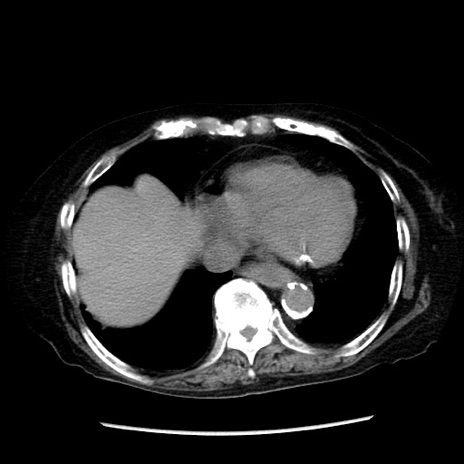

冠状断像